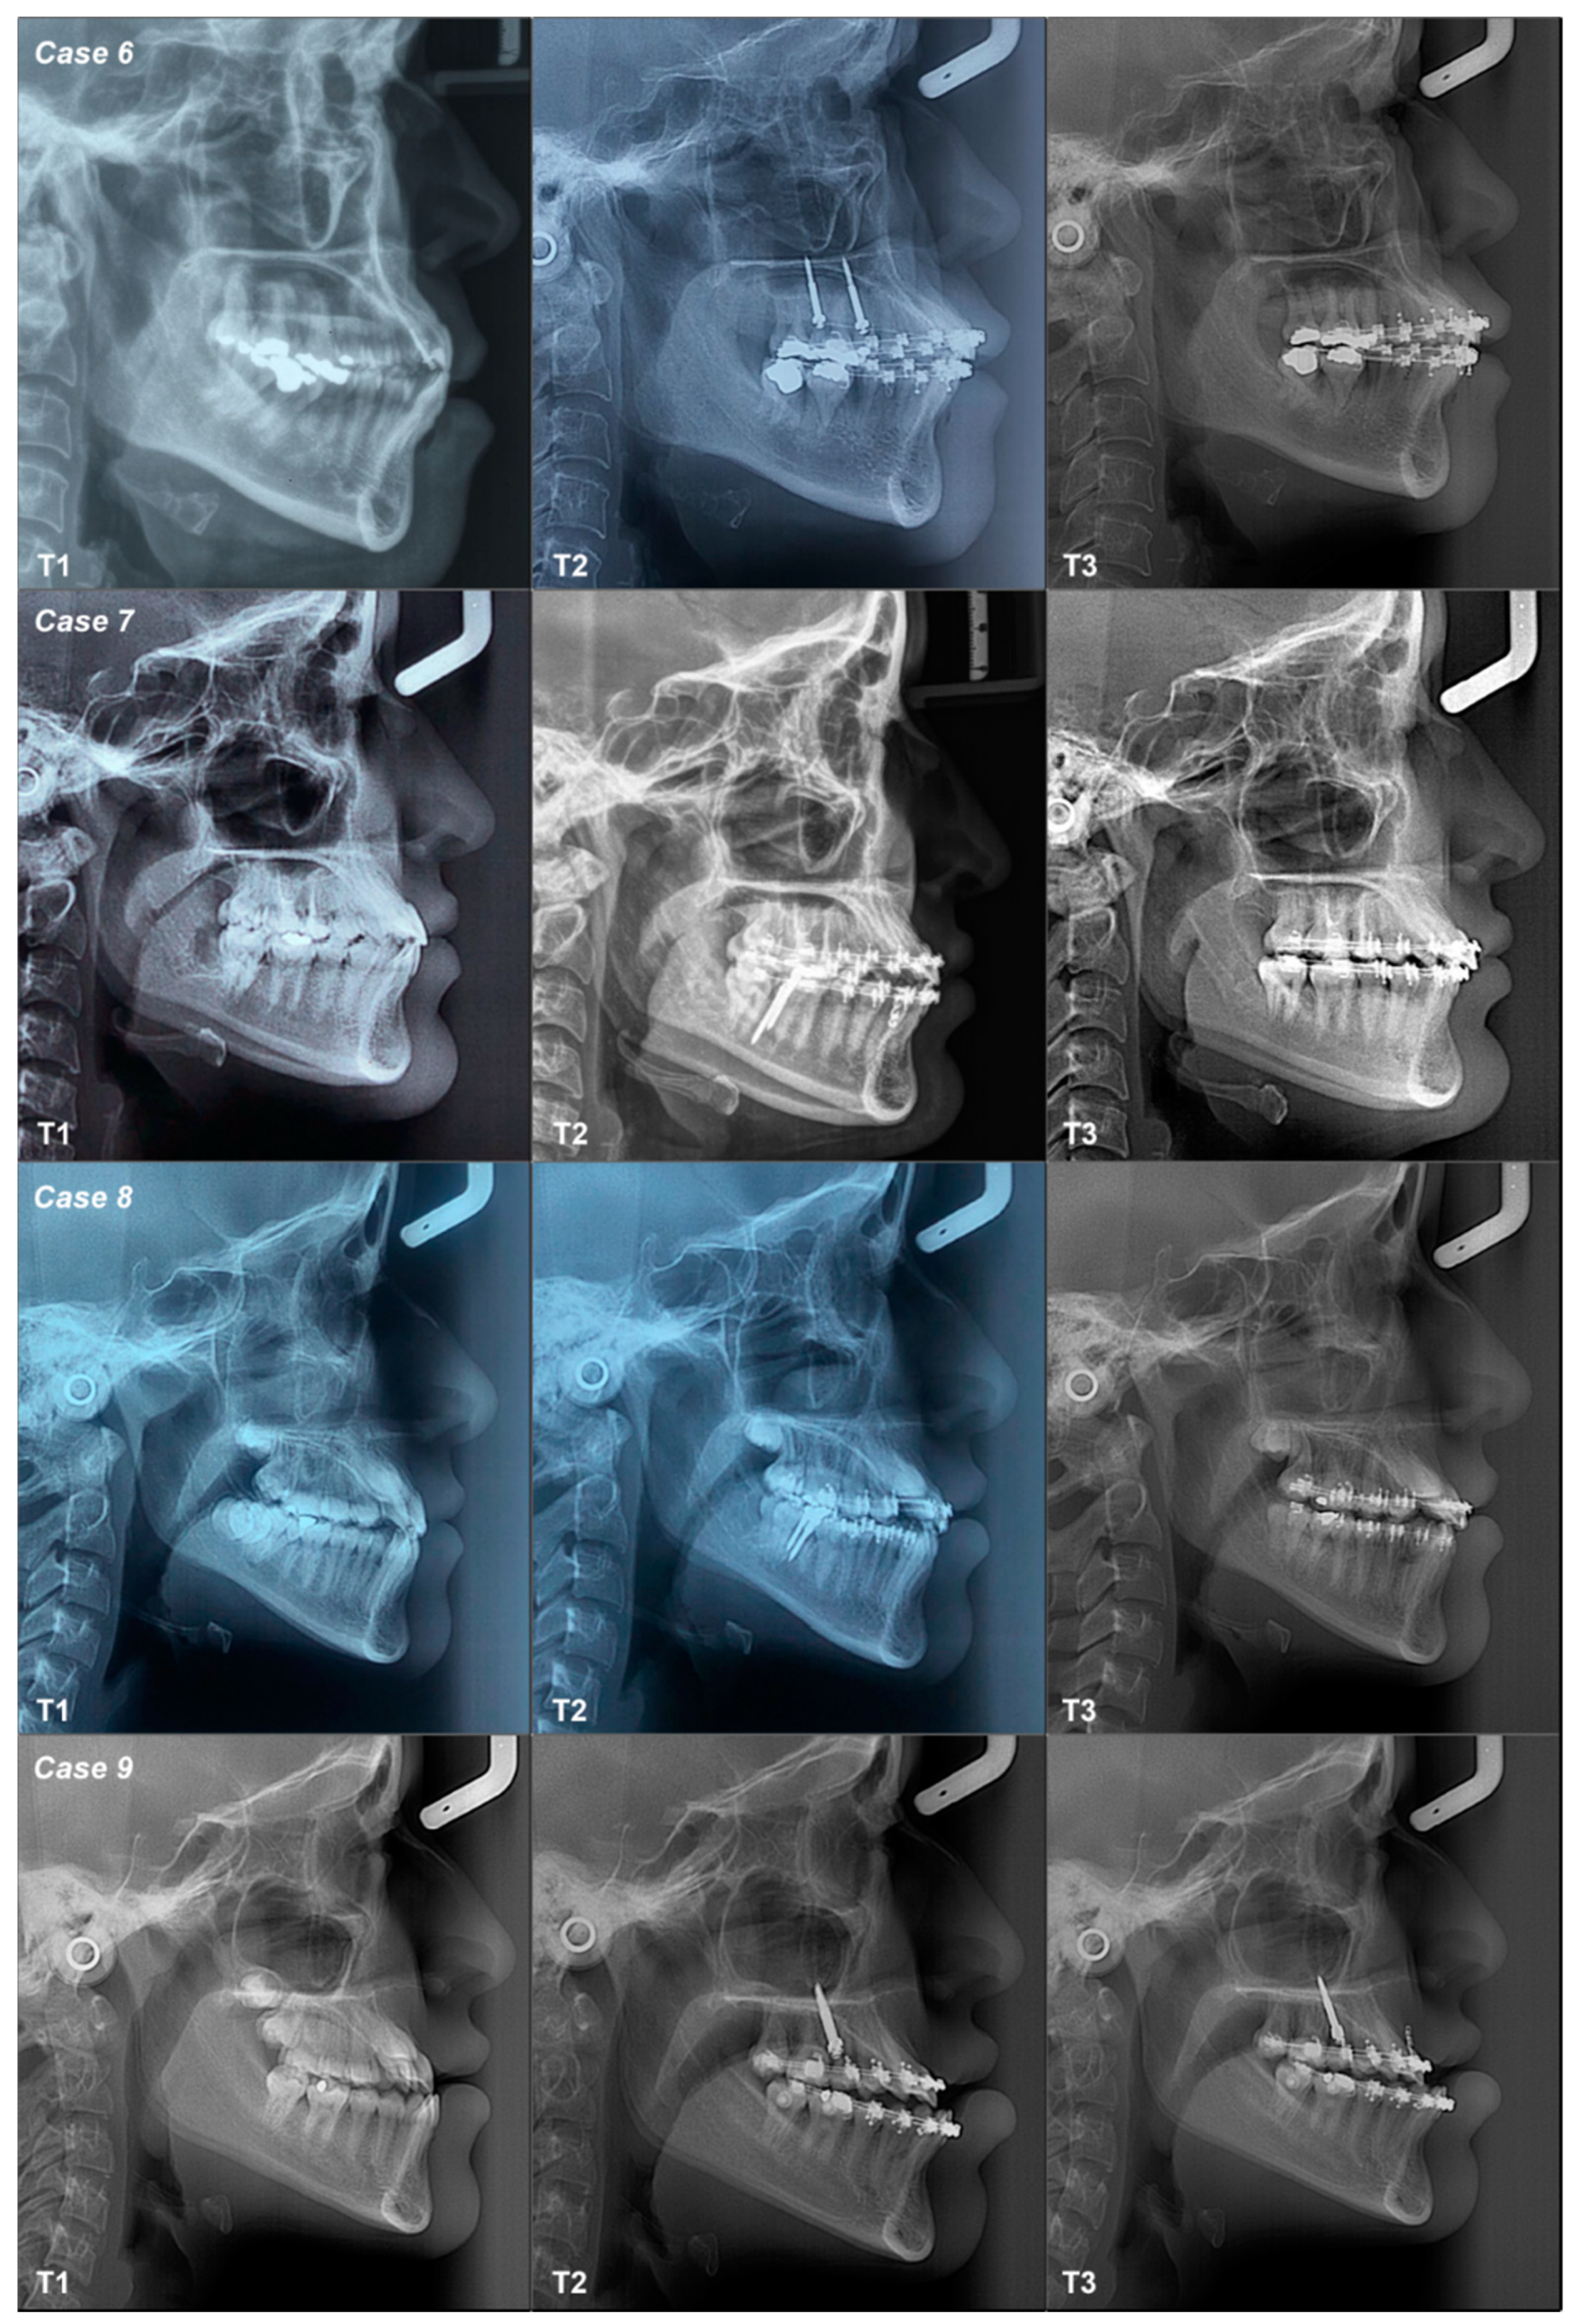

3.2.6. Case 6

3.2.7. Case 7

3.2.8. Case 8

3.2.9. Case 9

| 6 | Class III High Angle | Maxilla | T1–T2 | Flattened | Flattened | Flattened | Increased | Decreased | Decreased | Not changed | Not changed |

| T2–T3 | Flattened | Flattened | Tipped | Decreased | Increased | Decreased | Not changed | Not changed | |||

| T1–T3 | Flattened | Flattened | Flattened | Decreased | Decreased | Increased | Not changed | Not changed | |||

| 7 | Class III High Angle | Mandible | T1–T2 | Flattened | Flattened | Tipped | Decreased | Decreased | Decreased | Not changed | Not changed |

| T2–T3 | Tipped | Tipped | Flattened | Decreased | Increased | Decreased | Not changed | Not changed | |||

| T1–T3 | Flattened | Tipped | Flattened | Decreased | Decreased | Decreased | Not changed | Not changed | |||

| 8 | Class III High Angle | Mandible | T1–T2 | Tipped | Flattened | Flattened | Decreased | Increased | Increased | Not changed | Not changed |

| T2–T3 | Flattened | Tipped | Flattened | Increased | Decreased | Increased | Not changed | Not changed | |||

| T1–T3 | Tipped | Flattened | Flattened | Decreased | Decreased | Decreased | Not changed | Not changed | |||

| 9 | Class III High Angle | Maxilla | T1–T2 | Tipped | Tipped | Flattened | Decreased | Increased | Increased | Not changed | Not changed |

| T2–T3 | Flattened | Tipped | Flattened | Decreased | Decreased | Decreased | Not changed | Not changed | |||

| T1–T3 | Tipped | Tipped | Flattened | Decreased | Increased | Increased | Not changed | Not changed |